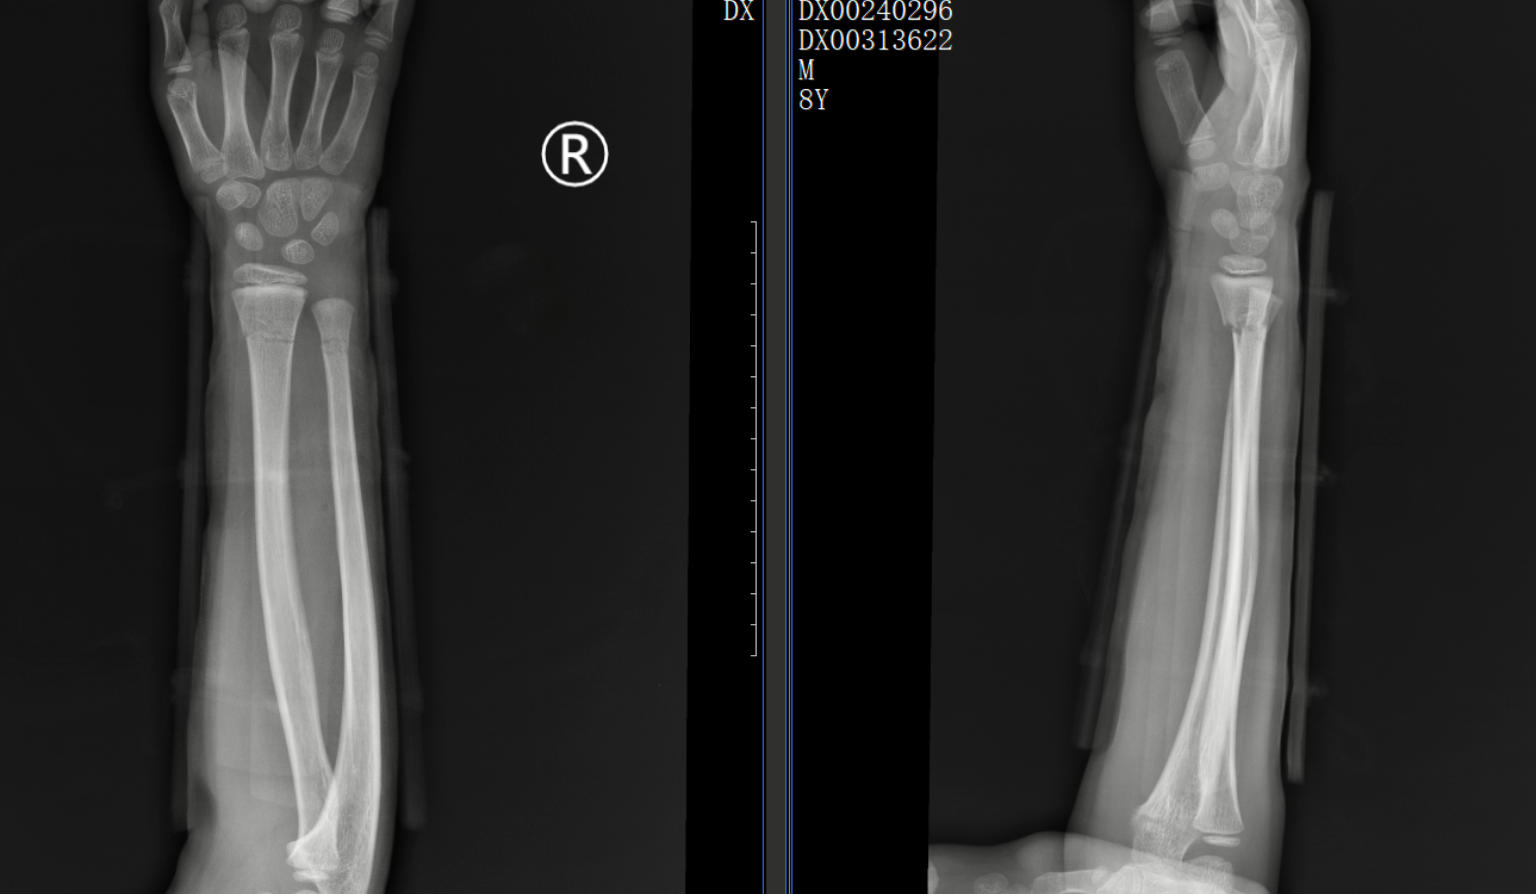

一位 8歲的學(xué)生在上學(xué)途中不慎摔傷,造成尺橈骨遠(yuǎn)端骨折。家屬心急如焚,為保守治療來到了我院中醫(yī)正骨中心就診。中醫(yī)正骨醫(yī)師運(yùn)用精湛的手法為小朋友進(jìn)行了復(fù)位,并配合夾板固定。3 周后骨痂形成,小朋友的功能活動也恢復(fù)良好。這一案例,讓家其屬深刻體會到了中醫(yī)正骨的獨(dú)特魅力。

正骨前后影像資料